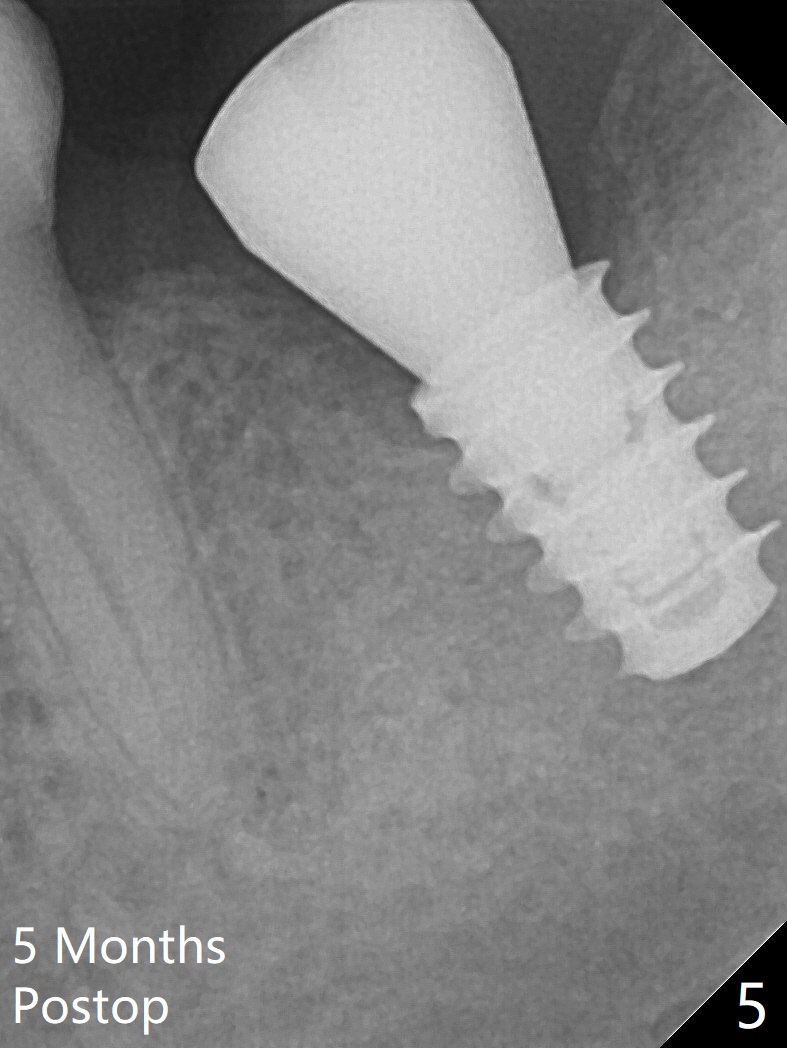

Six months post socket preservation at #18 (with moderate atrophy, Fig.1), a simplified surgical guide (Fig.2 with metal sleeve of 5 mm height and 2.93 mm diameter) determines initial osteotomy with 3.3 mm Magic Drill (MD), followed by 4.8 mm MD for 9 mm (gingival level) free hand. Since a 5x7 mm IBS implant is placed incompletely and in low stability (Fig.3 (in the graft bone)), a 4.3 mm MD is used for ~1 mm deeper. The implant is reseated to more satisfactory level (Fig.4: ~ 1 mm from the upper border of the Inferior Alveolar Canal (red dashed line)). The fearful patient is extremely pleased with quickness of the procedure as compared to that at #30 free hand. The wound heals normally 2 weeks postop. When she finishes the follow up appointment, she voluntarily talks to another patient who is hesitant about implant treatment. Impression is taken 5 months postop (Fig.5,6). There is no gap between the crown and abutment using abutcoping technique (Fig.7,8). The crown at #18 looks low probably related to long termed edentulism (Fig.9). The access hole is lingual (Fig.9), because the implant was placed lingual (Fig.10) due to use of a partial guide (Fig.11).